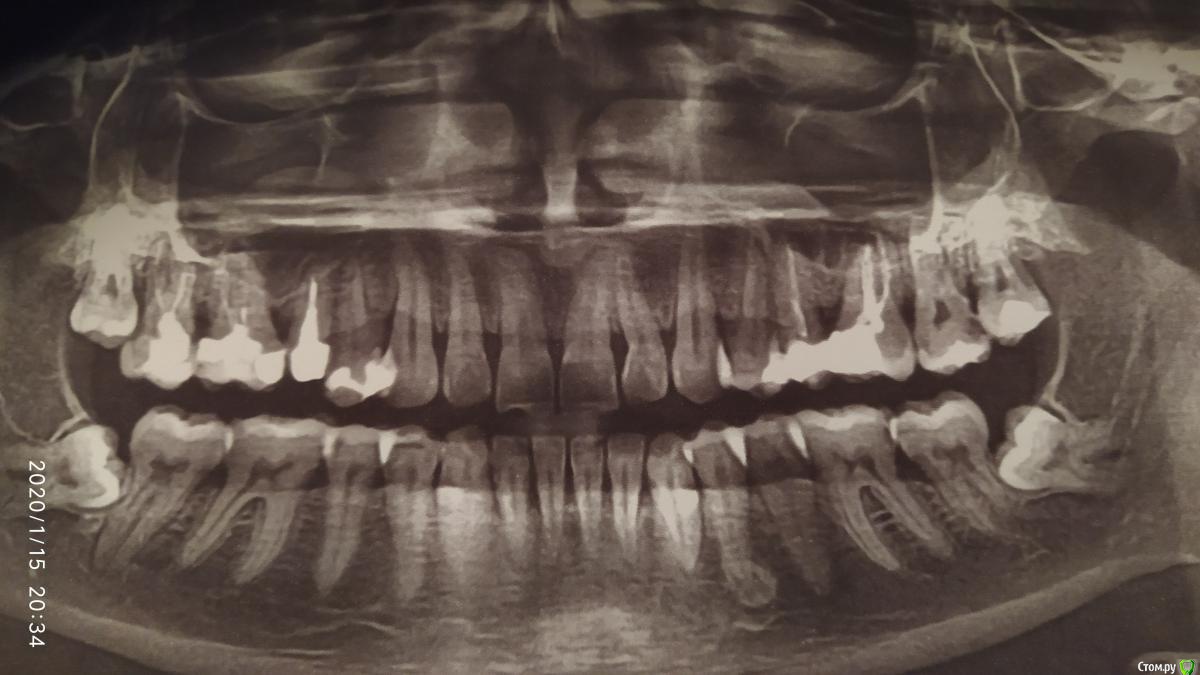

Goldi_V Опубликовано 15 января, 2020 Поделиться Опубликовано 15 января, 2020 (изменено) Добрый вечер. Где то месяц назад появился свищ над 5 зубом сверху слева. Сначала не придала значения, думала поранила чем то десну, но после обращения к стоматологу, сказал что свищ. Не могли бы Вы помочь разобраться со снимком, который делали примерно 2 месяца назад. На тот момент врач сказал что проблем больше нет(7 с кариесом уже запломбирован. 4 нижний слева сказали что такая анатомия, делали при цельные снимки). Имеется 2 вопроса: мог ли врач пропустить 2 месяца назад воспаление над 5 сверху слева (если оно тогда было) и шансы на успешное лечение. Зуб никогда не болел, но сейчас периодически пульсирует. Изменено 15 января, 2020 пользователем Goldi_V Ссылка на комментарий

Goldi_V Опубликовано 16 января, 2020 Автор Поделиться Опубликовано 16 января, 2020 Подскажите пожалуйста, а по панорамному снимку видно, было ли воспаление или нет? Ссылка на комментарий